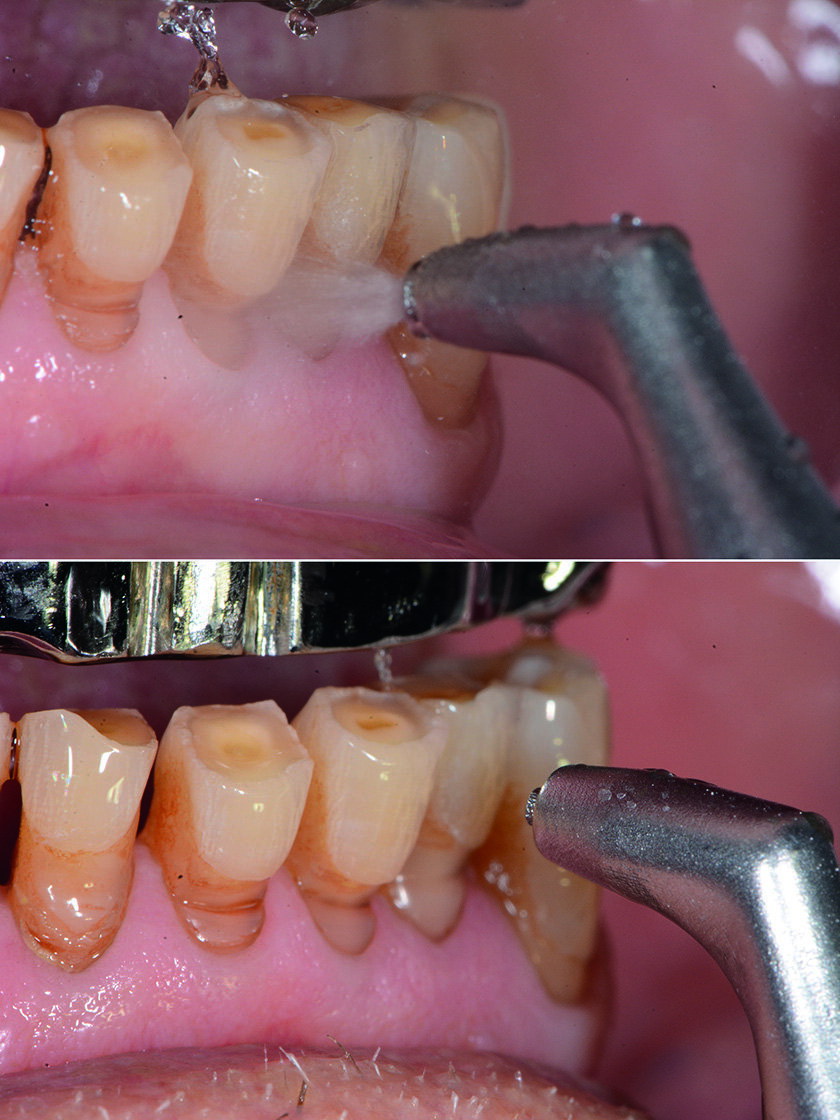

Debridment parodontale

Prima dell’intervento chirurgico si sottopone il paziente alla terapia parodontale non chirurgica degli elementi residui mandibolari. La scelta della tecnologia idonea per ogni quadro clinico è il primo obiettivo dell’approccio tailor-made anche in terapia parodontale non chirurgica (Nardi et al. 2014) che porta il professionista all’attenta osservazione delle caratteristiche anatomiche e tissutali, della presenza di eventuali patologie e delle caratteristiche delle superfici da trattare, permettendo delle operatività efficaci e minimamente invasive.

Usiamo airpolishing e polvere di glicina con il sistema di air-polishing Combi-touch (Mectron) in prossimità dei tessuti molli, mentre utilizziamo la polvere di carbonato di calcio Smooth (Mectron) a granulometria tra 45/75 µm a forma sferica con il vantaggio di arrivare nei siti ritentivi di biofilm batterico più adeso come a esempio per le zone interprossimali e per i margini gengivali (Fig. 14). Questa nuova tecnologia di polvere dà l’opportunità di lasciare le superfici trattate con un effetto brillante e non richiede il polishing successivo. Eseguiamo il debridement con il Combi-touch e la punta S1S e la punta in Peek (Fig. 15) ideale per i manufatti implantari. Il vantaggio ergonomico di eseguire il debridment con un ablatore multifunzionale piezoelettrico e un air-polisher con l’uso di polveri di carbonato di calcio e glicina sopra e sottogengivale permette una operatività clinica più agevole e meno fastidiosa per il paziente. L’opportunità di poter usare i manipoli orientati a 90° o 120° permette di poter essere efficaci nel rispetto della delicatezza dei tessuti e del manufatto implantare, erogando il getto in maniera personalizzata e mirata, con un’operatività clinica minimamente invasiva.